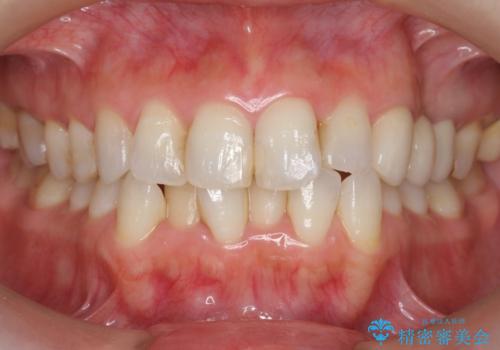

つぎはぎの前歯をセラミックにしたい

- 保険治療のプラスチックでつぎはぎの歯をセラミックにし、一緒に前歯の並びもきれいにしたいとのご希望でした。

色や形については納得いくまで修正し、最後は満足されていました。